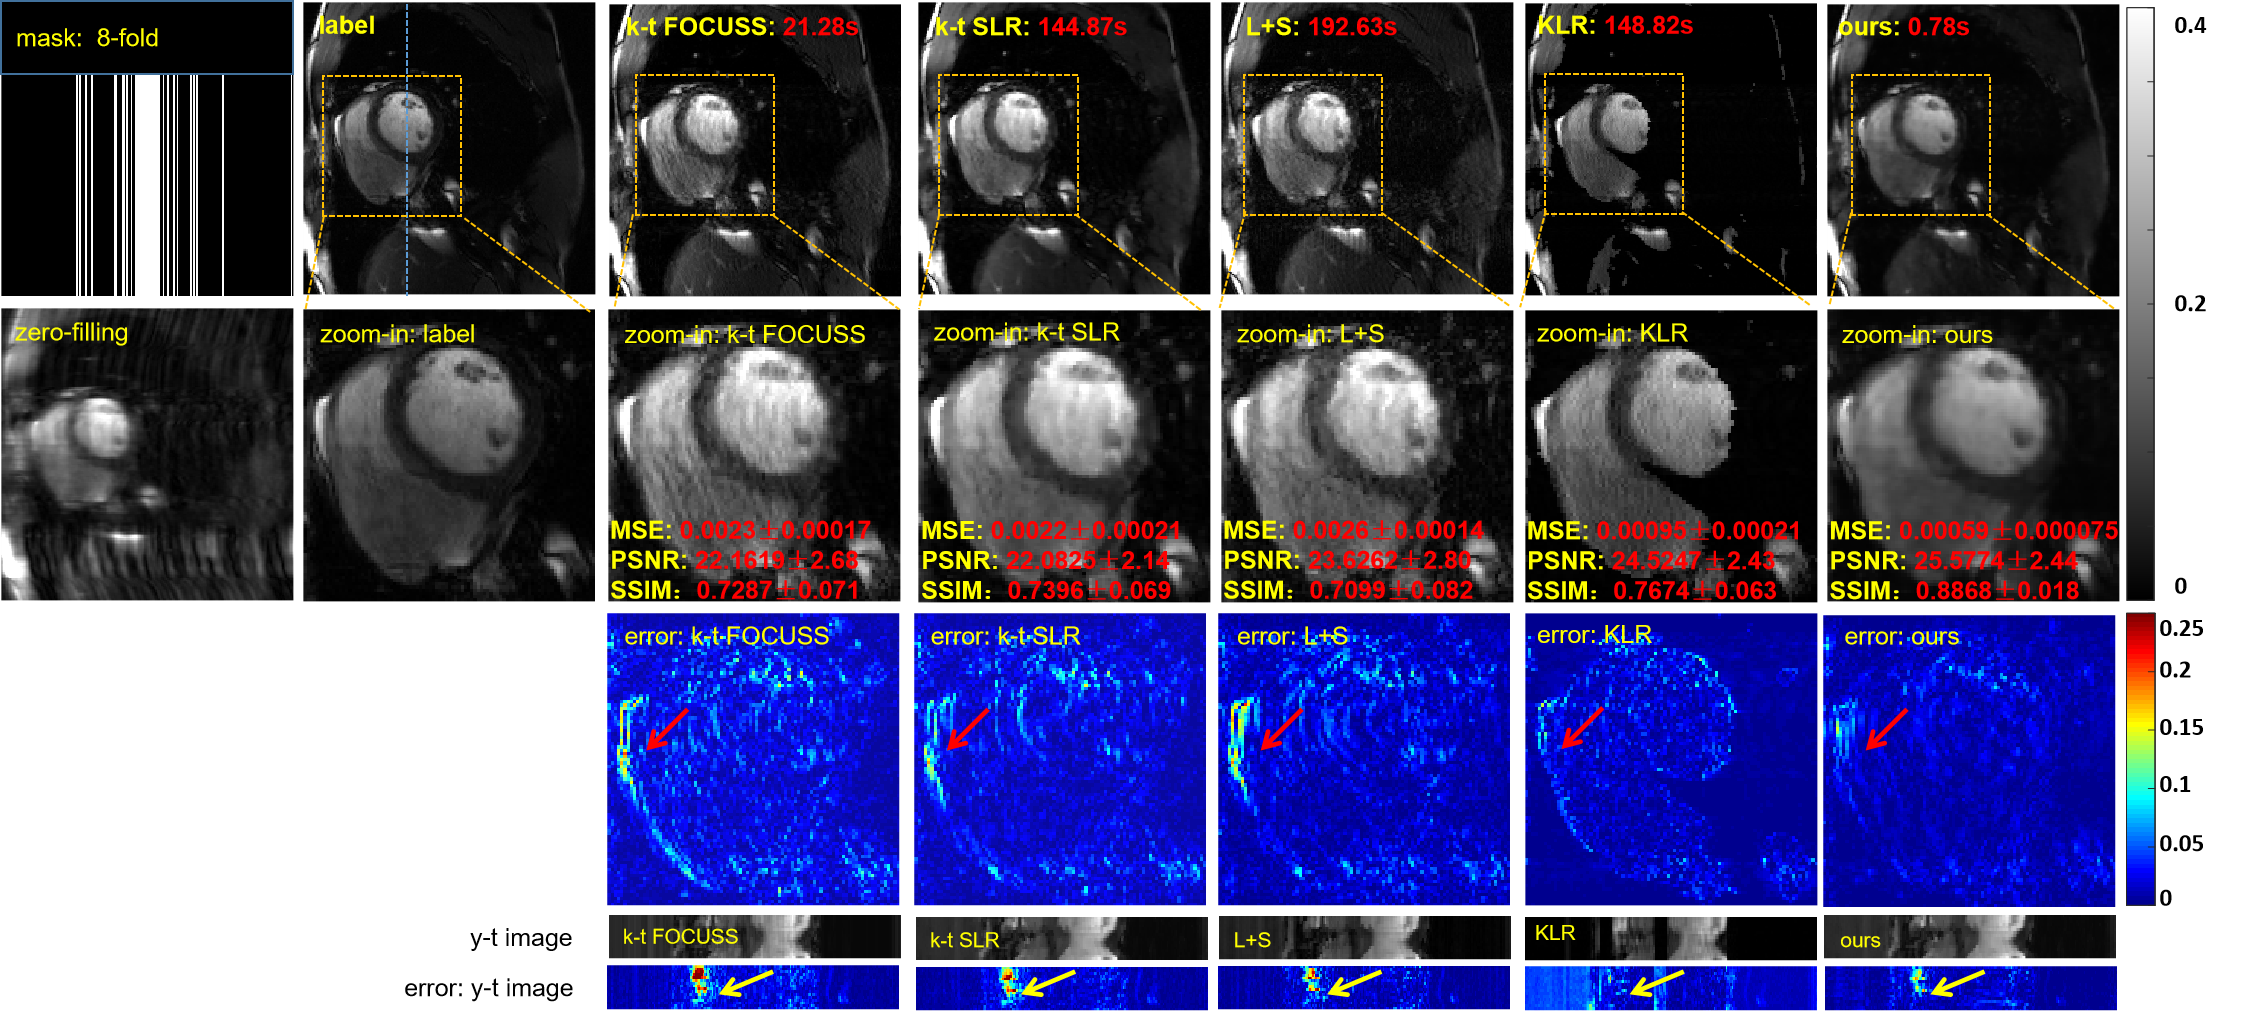

To demonstrate the efficacy of the proposed unsupervised learning method, we compared it with several state-of-the-art CS/LR methods including k-t FOCUSS [6], k-t SLR [11], L+S [10] and KLR [12]. We adjusted the parameters of the competing methods to elicit their best performance. A 1D random Gaussian mask was used for training and testing. The reconstruction results of these methods at 4-fold acceleration are shown in Fig.5. The reconstruction results of the four CS-based methods contain fewer structural details and more artifacts than do the reconstruction results of the proposed method. We also enlarged the cardiac region and its error map for demonstration to show that our method achieves the best reconstruction performance in the cardiac region, especially the details marked by the red arrow. The y-t image and its error map, which were extracted from the 124th slice along the y and temporal dimensions, also clearly illustrate the superior performance of the proposed method. The evaluation indexes, MSE, PSNR, and SSIM, can be found in the enlarged view of the heart regions. All the quantitative results shown are the averaged results on the test data set, and the standard deviations are also given. We observe that the MSE, PSNR and SSIM indexes of the proposed method are the best among all the methods. The red numbers represent the reconstruction time of these methods for the entire volume. Our method also has the shortest reconstruction time–hundreds of times shorter than those of the other methods.

The reconstruction results of the different methods at 8-fold acceleration are shown in Fig.6. At 8-fold acceleration, we can reach the same conclusion as with 4-fold acceleration.